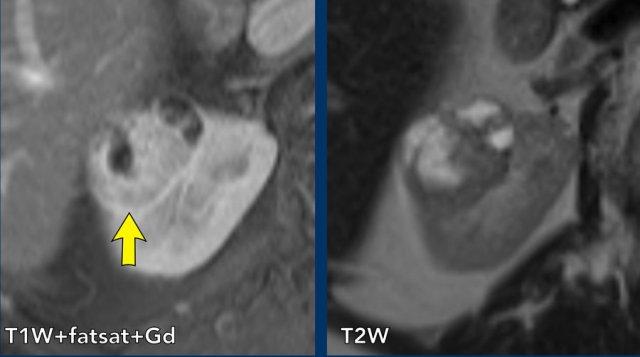

Ca lâm sàng 2

Các hình ảnh cho thấy một khối dạng nang với thành dày (< 4mm) và một vài vách dày không đều.

Trên các ảnh sau tiêm thuốc tương phản từ, không ghi nhận ngấm thuốc của vách hoặc thành, nhưng có thể xác định rõ ràng một nốt thành ngấm thuốc (mũi tên).

Do đó, đây là tổn thương Bosniak IV. Tổn thương đã được phẫu thuật cắt bỏ và được xác nhận là ung thư biểu mô tế bào sáng (clear-cell carcinoma).